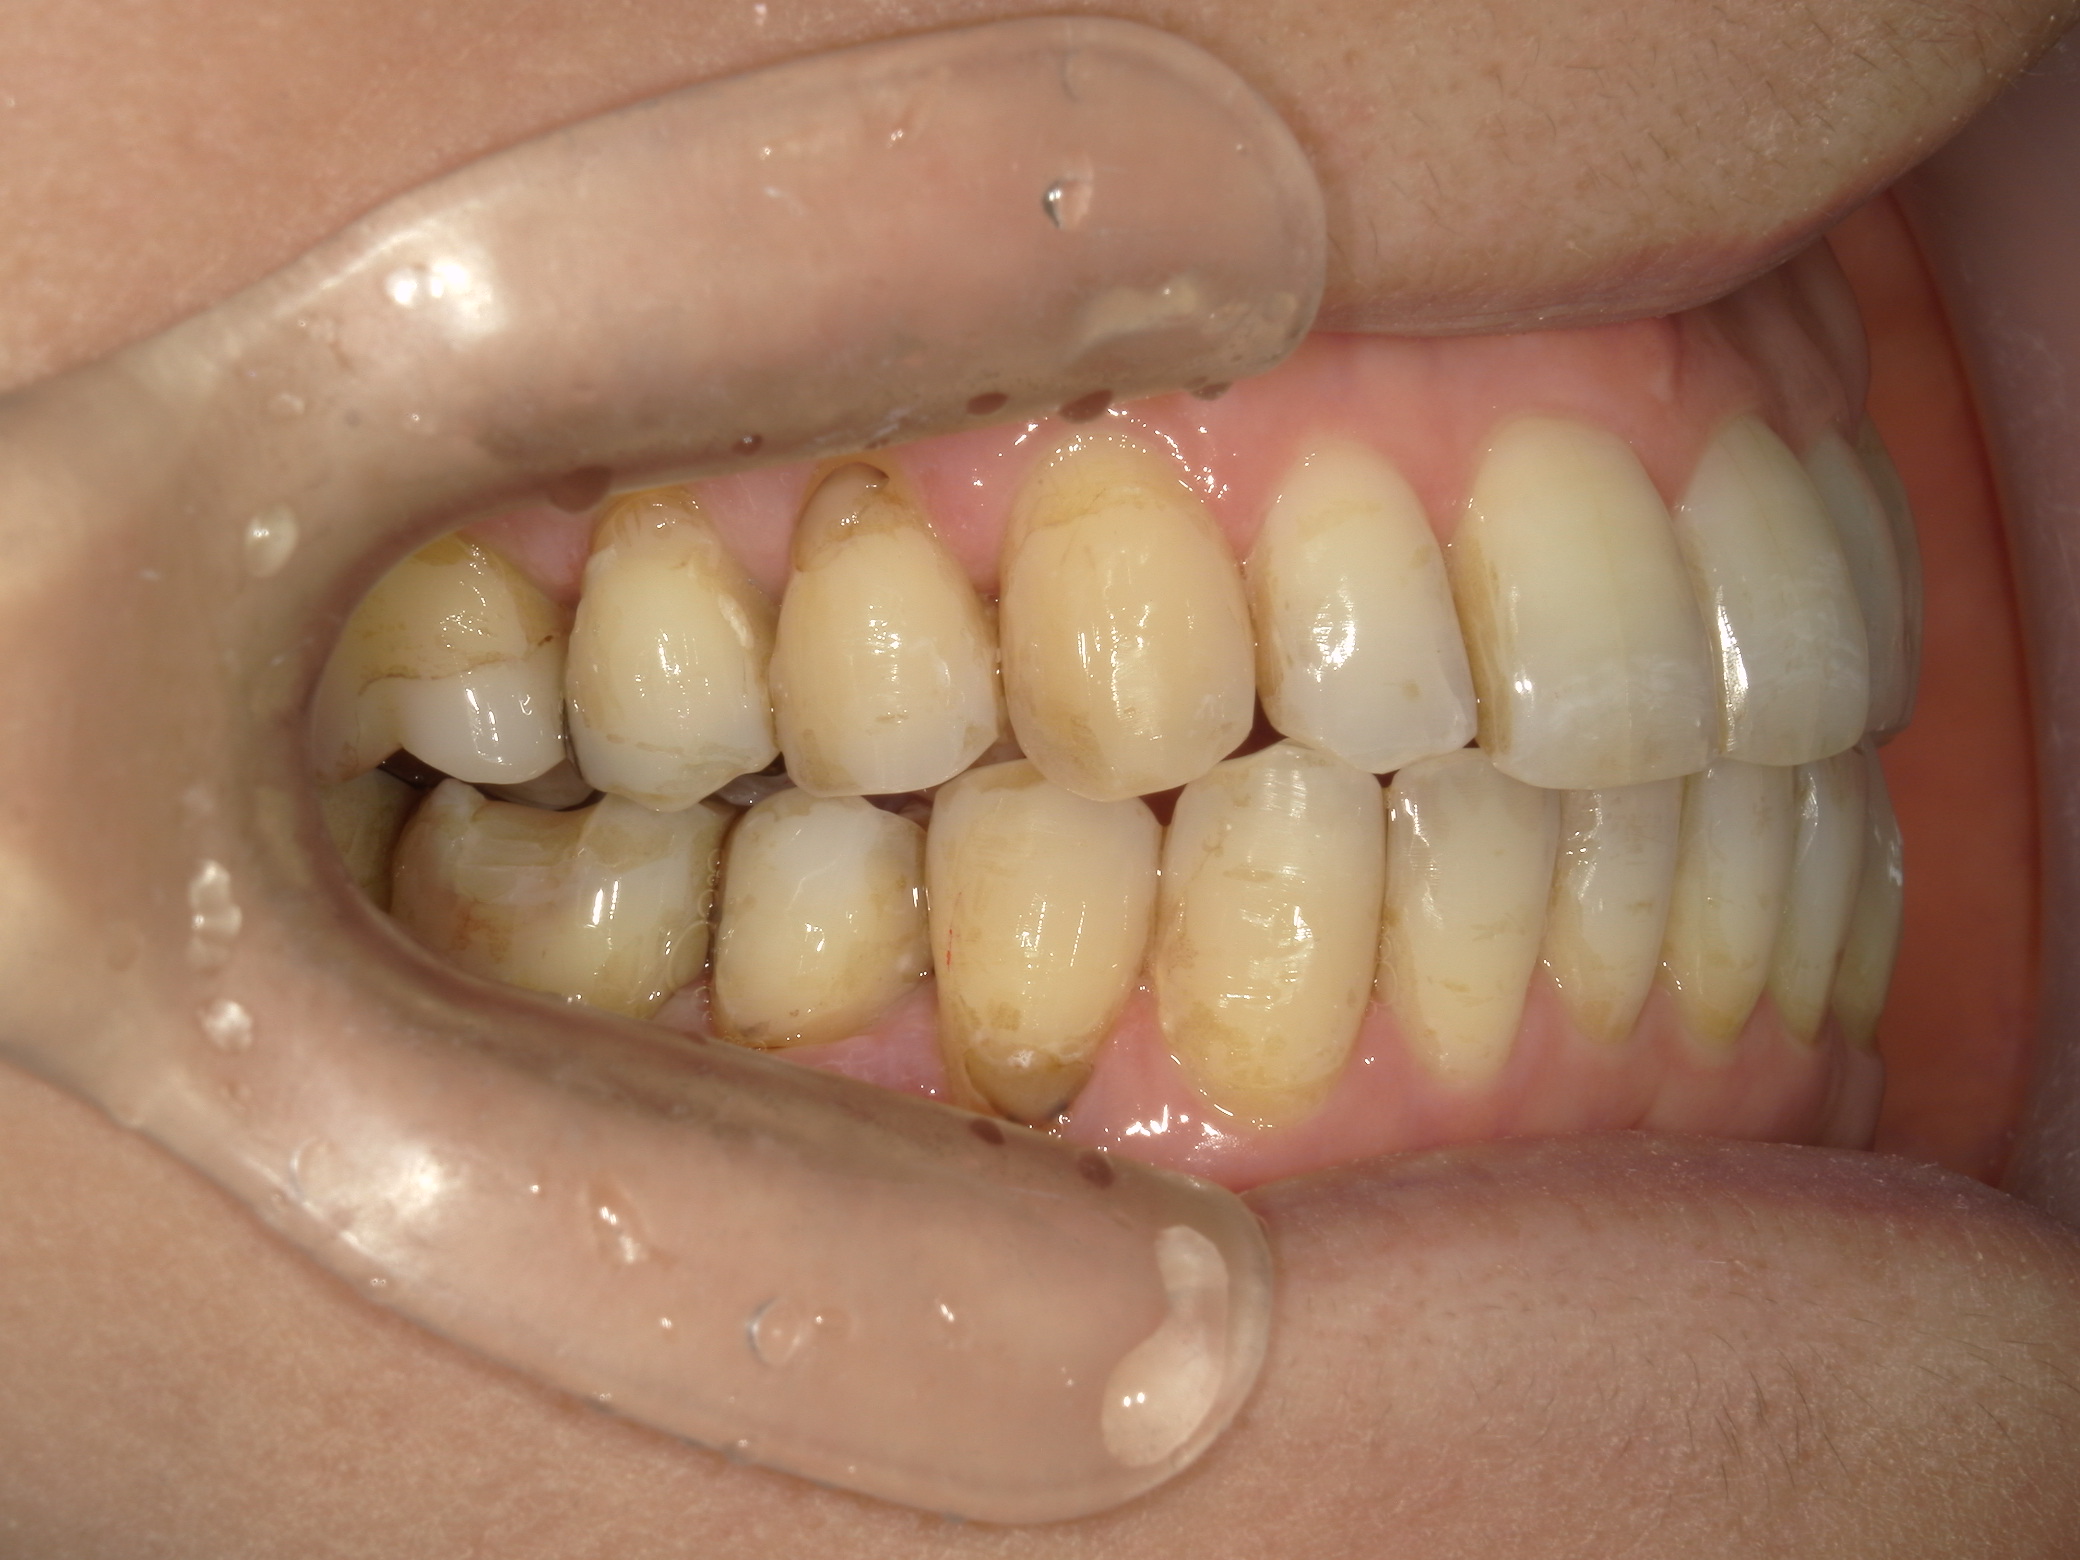

インビザライン矯正 症例(25)

主訴: ㊤前歯が出ていて、噛み合わせが気になる。

カテゴリー : ガタガタ(叢生)